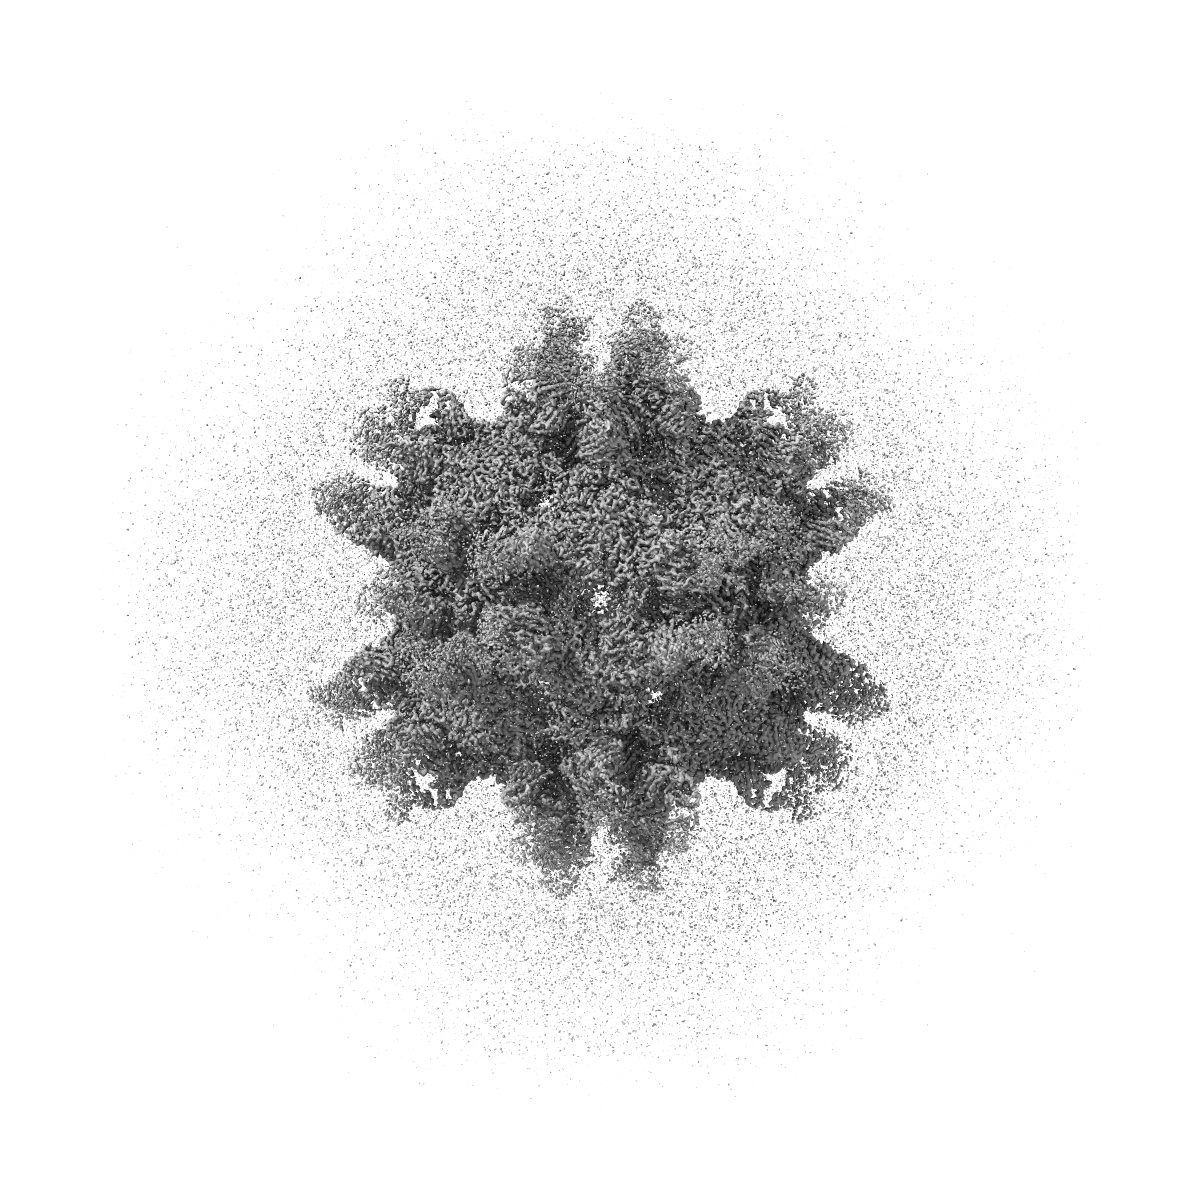

Cryo-EM structure of Coxsackievirus B1 empty particle in complex with nAb 8A10 (CVB1-E:8A10)

Single-particle3.52 Å